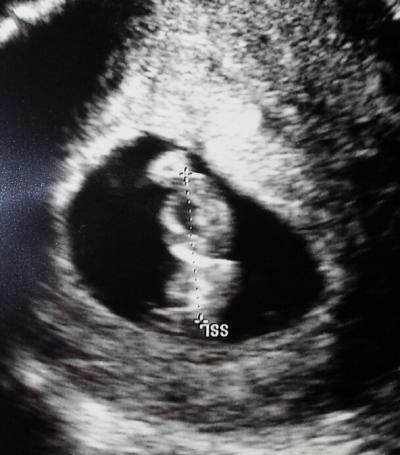

Alles in bester Ordnung. zwergi ist genau zeitgerecht entwickelt mit etwa 17mm. ET wurde nun festgesetzt auf den 17.4 entspricht auch meiner Berechnung. den mutterpass habe ich nun auch und die Schwester fragte gleich ob ich einen neuen will fürs zweite Kind. scheinbar konnte sie mir den Wunsch von den Augen ablesen :-) der Pass hat auch eine süße hülle. beim nächsten Termin können mein Mann und Sohn dann auch endlich mit rein. wollen uns den gemeinsamen vaginalen us lieber sparen. der kleine würde wohl von nix anderem mehr erzählen..... nur das Thema ersttrimesterscreening bleibt offen. uns würde ja die reine nackenfaltenmessung reichen aber das fand die Ärztin komisch. mal sehen.

Bild zu zurück vom gyn - Forum für April - Mamis